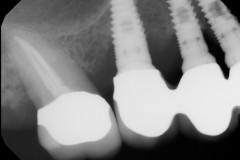

This young patient was self-conscious about the appearance of her short teeth and gummy smile. Through crown lengthening and tooth whitening procedures, we were able to create a beautiful, more mature smile.

Click on a thumbnail to view the before and after photos.